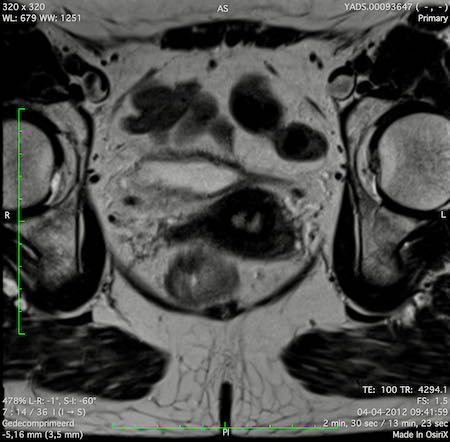

Hình ảnh

Các hình ảnh được cung cấp cho thấy ung thư biểu mô tế bào nhẫn với tình trạng dày lan tỏa thành trực tràng, hình ảnh bia bắn điển hình, và sự xâm lấn mỡ mạc treo trực tràng.